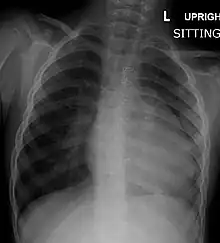

A chest X-ray of a child with tetralogy of Fallot

Chest radiograph

Before more sophisticated techniques became available, chest X-ray was the definitive method of diagnosis. The abnormal "coeur-en-sabot" (boot-like) appearance of a heart with tetralogy of Fallot is classically visible via chest X-ray, although most infants with tetralogy may not show this finding.[49] The boot like shape is due to the right ventricular hypertrophy present in TOF. Lung fields are often dark (absence of interstitial lung markings) due to decreased pulmonary blood flow.[50]:171–72